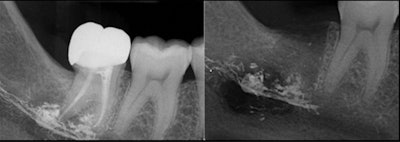

A 27-year-old woman lost sensation in her chin and lip following root canal treatment on her mandibular molar. Months later, specialists confirmed that extrusion of the root canal sealer caused the patient's permanent anesthesia, according to a case report in Oral Surgery.

On the left, a dental x-ray shows apical radiolucency, with superimposed radiopaque sealer material extruding at the root tips of endodontically treated tooth #47. On the right, the x-ray shows its presence in socket 47 after extraction. Image courtesy of Mahmood et al. Licensed CC BY 4.0.

Imaging showed that the root canal sealer was widespread within the marrow spaces where endodontic treatment had occurred. The sealer extended to the mandibular canal and perforated the mandible's lingual cortex.